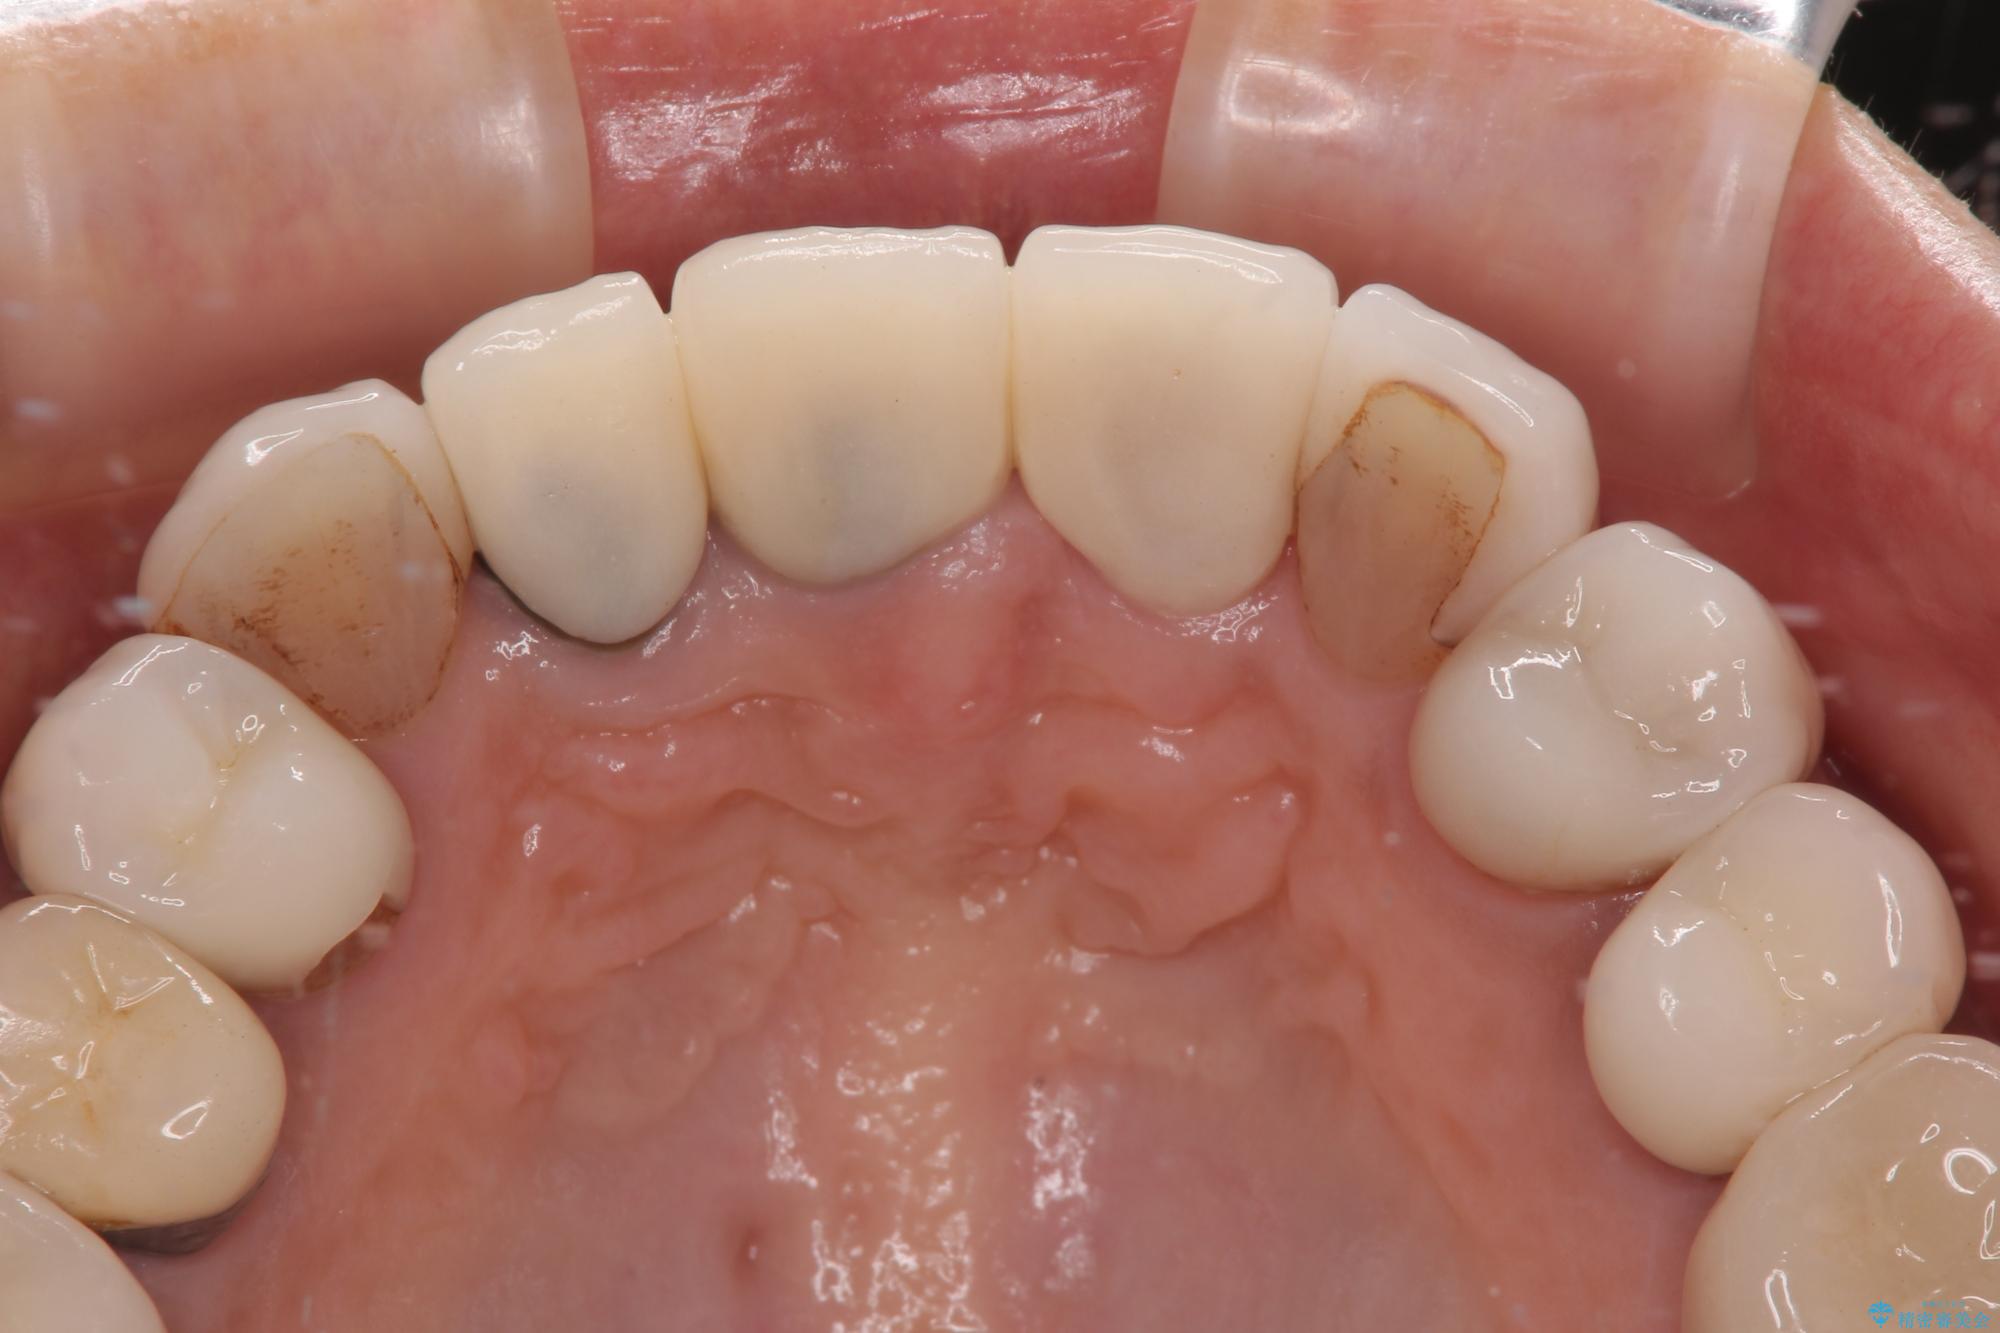

色調が統一されるだけでなく、歯肉ラインに見えていた茶色の境目も綺麗に改善されました。

20年以上前から、むし歯になったり詰め物が欠けたりする度に部分的に処置を行ってきたそうですが、この際統一感のある前歯にしたいとのことで、上顎前歯9本をオールセラミッククラウンによる補綴治療を行うこととしました。